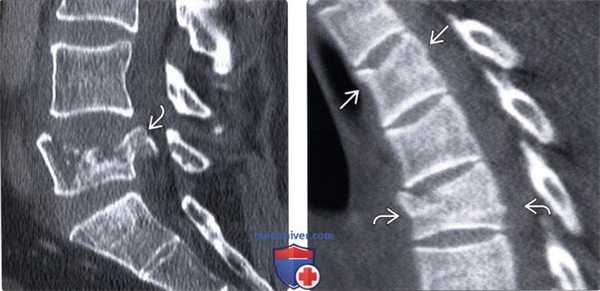

(Слева) КТ, сагиттальный срез (костный режим): перелом, линия которого проходит в области нижней части тела позвонка параллельно замыкательной пластинке. Передний отдел зоны перелома расширен, что свидетельствует о гиперэкстензионном повреждении.

(Справа) На сагиттальном STIR МР-И отмечается патологические усиление сигнала в области передней продольной связки и нижней части тела позвонка. В области задней продольной связки и задних элементов достоверных признаков изменения сигнала не видно.

(Слева) КТ, сагиттальный срез, пациент с анкилозирующим спондилитом: гиперэкстензионный переломовывих. Нижележащий отдел позвоночника смещен кпереди, что привело к критическому стенозу спинномозгового канала. Каудальней виден компрессионный перелом позвонка.

(Справа) КТ, сагиттальный срез: косой перелом тела среднегрудного позвонка с незначительным расхождением фрагментов, свидетельствующим о гиперэкстензионном характере повреждения. В области двух нижележащих позвонков видны вертикальные линии переломов.